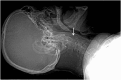

Emergency and trauma care produces a "perfect storm" for radiological errors: uncooperative patients, inadequate histories, time-critical decisions, concurrent tasks and often junior personnel working after hours in busy emergency departments. The main cause of diagnostic errors in the emergency department is the failure to correctly interpret radiographs, and the majority of diagnoses missed on radiographs are fractures. Missed diagnoses potentially have important consequences for patients, clinicians and radiologists. Radiologists play a pivotal role in the diagnostic assessment of polytrauma patients and of patients with non-traumatic craniothoracoabdominal emergencies, and key elements to reduce errors in the emergency setting are knowledge, experience and the correct application of imaging protocols. This article aims to highlight the definition and classification of errors in radiology, the causes of errors in emergency radiology and the spectrum of diagnostic errors in radiography, ultrasonography and CT in the emergency setting.